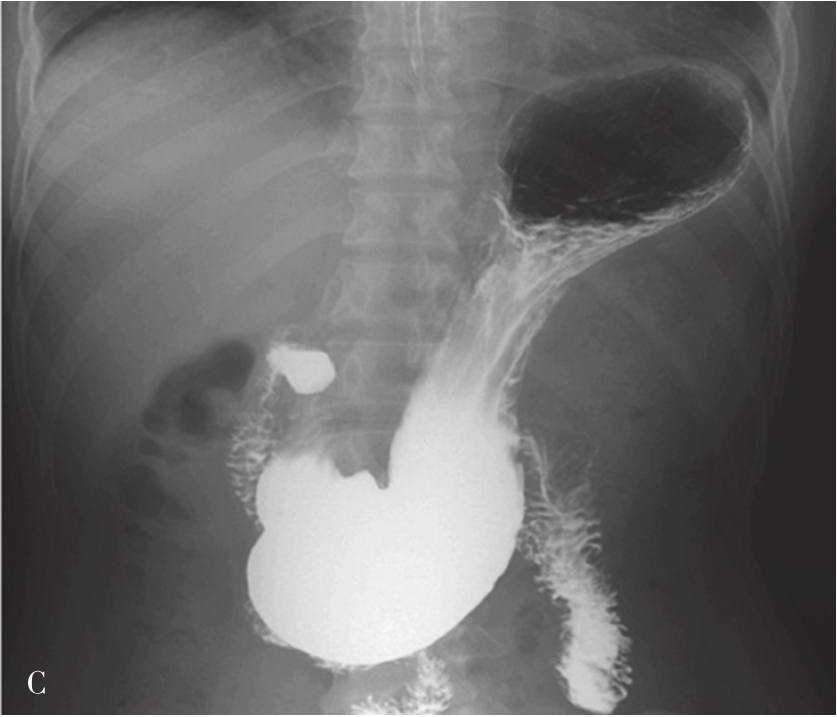

内镜逆行胰胆管造影(endoscopic retrograde cholangiopancreatography,ERCP)指将十二指肠镜插至十二指肠降部,找到十二指肠乳头,由活检管道内插入造影导管至乳头开口部,注入造影剂后进行X线透视和摄片,以显示胰胆管的技术。临床上是显示胰胆管的主要方法之一。它使成像的胆管系统可达到最大可能的范围,若插管成功,注入造影剂,可见内镜逆行胰胆管造影(图5-21-45)。同时可以进行各种治疗程序。如胆总管结石的诊疗中,以往需要外科手术治疗,存在手术创伤大、术后恢复慢、结石残余或复发等难题。在采用ERCP后只需通过十二指肠乳头小切口,即可对肝外胆管结石(图5-21-46)进行碎石、取石、清理等操作。ERCP最早的报道在1968年,随着器械和技术的进步,而在临床上得到推广应用。目前,临床上应用ERCP并不是单纯为了诊断胆管系统的疾病,因为已有了更微创和有效的手段,如磁共振胰胆管成像(magnetic resonance cholangiopancreatography,MRCP)和超声内镜(endoscopic ultrasound,EUS),而主要应用在处理胆道的疾病。适应证主要有胆道梗阻引起的黄疸,如急性胆管炎、胆总管结石、胆道狭窄、胆漏、胆道出血和Oddi括约肌功能紊乱等。内脏穿孔为绝对禁忌证,凝血功能异常、无并发症的急性胰腺炎和心肌梗死都是相对禁忌证。以下简述其技术方法:

图5-21-45 内镜逆行胰胆管造影法示胰胆管

可见胆囊及胆系树枝状影像,并清晰显示胰管走行

图5-21-46 内镜逆行胰胆管造影法示肝外胆管结石

可见胆总管(CBD)内结石(GS)影像(直径大于2cm)

ERCP采用有侧视(side-viewing)的十二指肠镜,经口送入十二指肠后,通过灯光观察到十二指肠乳头,并且可以侧视孔插管进入胆总管内。操作需要在透视下完成。胆管插管成功后,可以注入造影剂显示肝内外胆管(图5-21-47)。正常胆总管直径小于6mm。胆囊切除术后和年龄大于70岁者,胆管直径可能达到9~10mm。也可以引入导丝和其他器械,以进行诊断和治疗。应用括约肌切开器切开十二指肠乳头,有利于其他器械引入到胆管内。

有经验的内镜医生ERCP的成功率可达90%~95%,行Billroth Ⅱ胃肠吻合术后,技术成功率可下降到60%。ERCP不成功的患者,可以选择经皮肝穿刺胆道造影。ERCP也是一种有创的手段,且可发生并发症,最常见是急性胰腺炎,发生率为2%~5%。另外,还可能有出血或穿孔等,发生率均低于1%。

经皮肝穿刺法(percutaneous transhepatic cholangiography,PTC):即使用细穿刺针,自右腋中线或剑突下径路,在超声或X线监视引导下,穿刺入肝内胆管,再注入造影剂以显示肝内外胆管,可了解胆管的形态,胆管病变部位、程度和范围,观察胆汁的胆管内流动和分布的情况,为诊断胆管病变提供影像学证据(图5-21-48)。PTC是一种具有悠久历史的检查方法,最早于1937年被报道。但随着器材和引导技术的进步,直到近30年在临床上才得到广泛重视。PTC主要用于梗阻性黄疸患者,以了解胆管梗阻部位、范围和原因。不能纠正的出凝血功能严重障碍是本术的禁忌证。近期心肌梗死病史,间位结肠和大量腹水患者是相对禁忌证。本术系有创性检查,亦可造成腹腔出血、胆瘘、胆汁性腹膜炎等并发症。目前,临床上已少用PTC单纯诊断胆管病变,而是为后续的经皮肝穿刺胆道引流(percutaneous transhepatic cholangial drainage)或进行其他的胆道疾病的处理打下基础。以下简述其技术方法:

图5-21-47 ERCP拔除内镜后显示肝内外胆管及胰管

拔除内镜后可见肝内外胆管和胰管显影。胆总管内结石影,直径大于6mm

图5-21-48 经皮肝穿刺法胆管造影

胆囊切除胆肠吻合术后,经皮肝穿刺法(PTC)获得的肝内外胆管形态影像,并可观察到肝胆管内结石和胆汁在胆管内流动的情况。